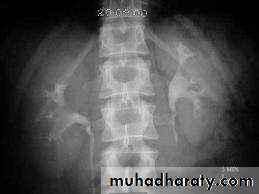

4. Full length film after release of compression .

Urinary tract